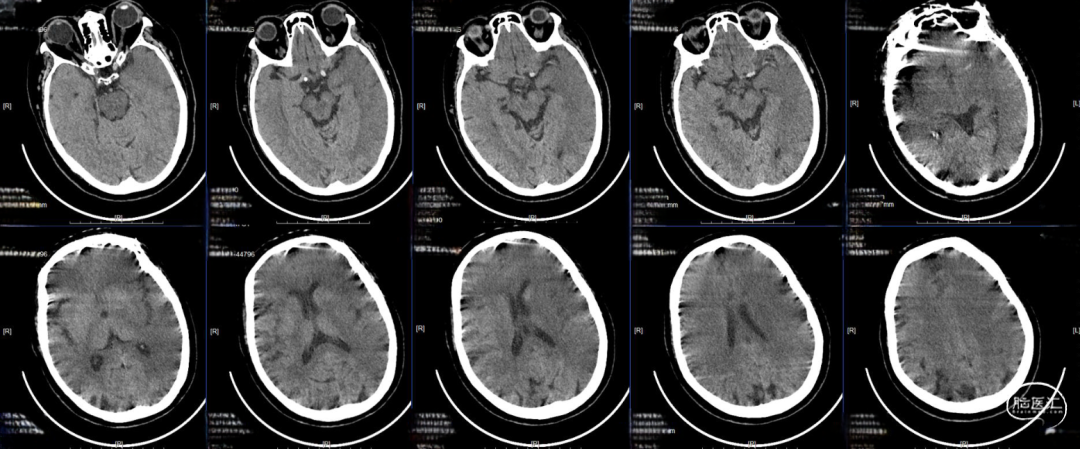

现病史:患者于2022年9月19日下午15点家务时突然出现右侧肢体无力并伴有不能言语,无发热、抽搐,当地医院急诊头颅CT提示左侧基底节区低密度病灶,未溶栓,立即送来我院,途中出现意识减退。

CT-ASPECT评分2分。

头颈部CTA cbs评分9分。

术后24小时复查CT,高灌注、轻肿胀,未见明显出血,轻度镇静至停用镇静,过程中可唤醒,自然复苏,呼吸机维持。

术后48小时复查CT,左半球大片低密度病灶、中线偏移,有主动睁眼、遵嘱动作,暂停呼吸机,延迟拔管,备去骨瓣。

术后96小时复查CT,左侧半球肿胀未继续进展,嗜睡,易唤醒、有睁眼、遵嘱动作,右侧肢体有自主动作,拔除气管插管。

术后第14天启动抗凝,术后第19天复查CT,术后第20天出院,NIHSS评分8分,mRs评分4分。

术后门诊随访,术后2月时mRS评分3分,术后4月时mRS评分2分,6月时随访mRS评分2分。